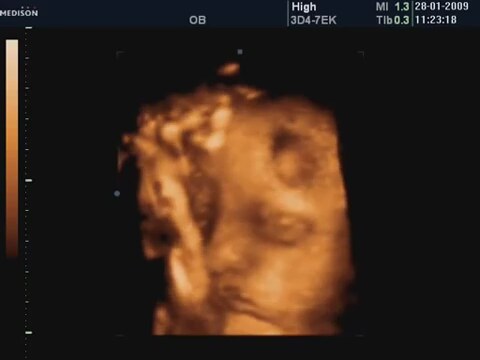

30 Haftalık Bebeğin 4 Boyutlu Ultrason Görüntüsü